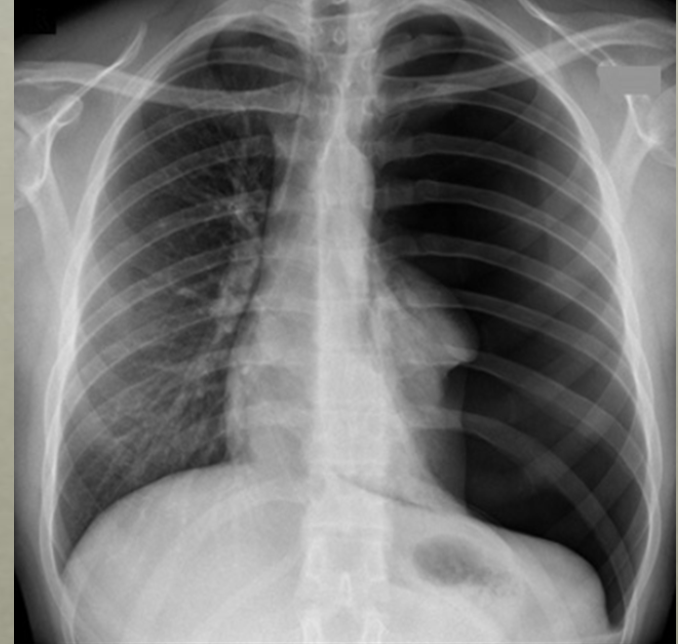

C - Cardiac Silhouette and Mediastinum:

* Normal heart size = <50% of thoracic width (PA) view

* Enlarged heart (>50%) –> cardiomegaly, pericardial effusion

notice the cardiac thoracic ratio